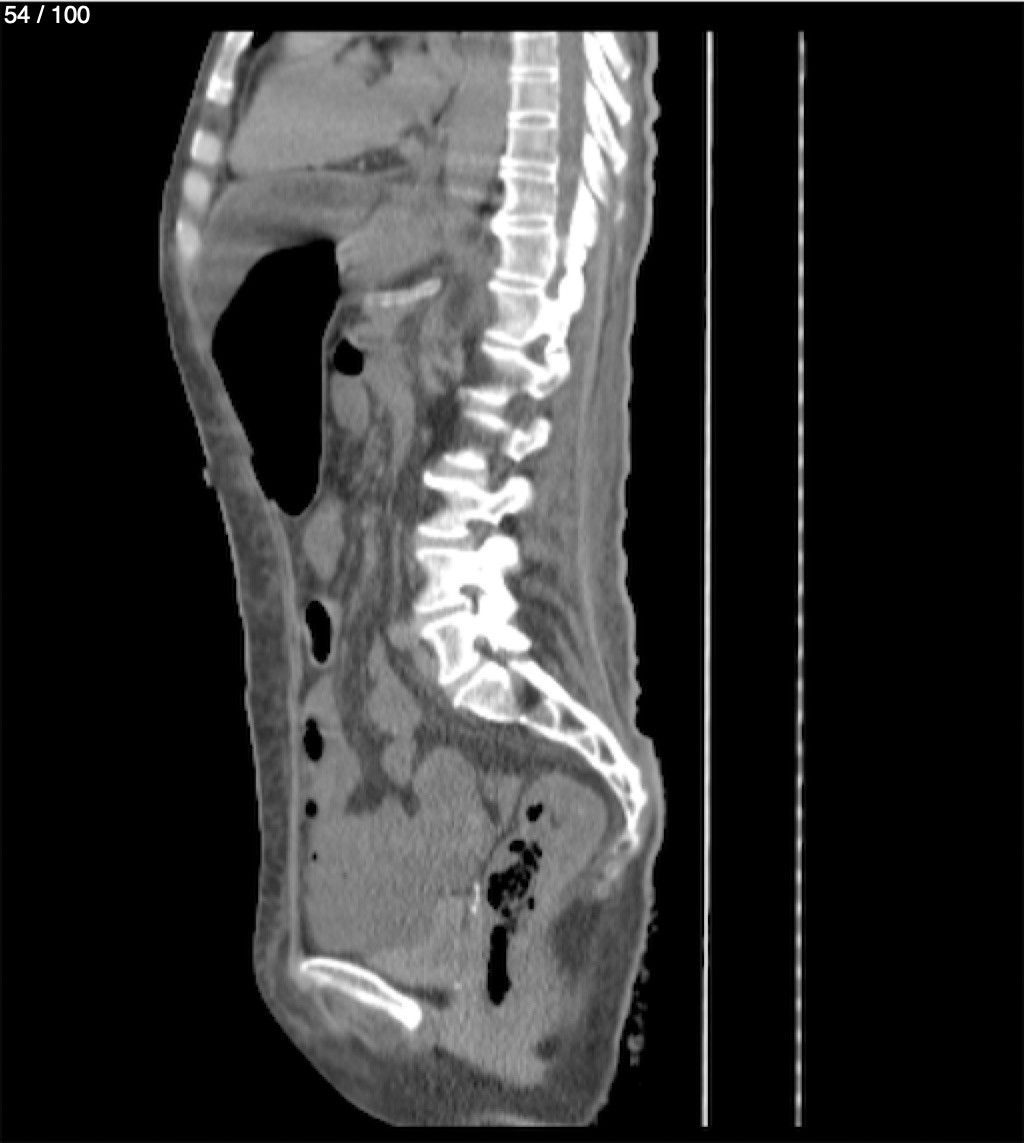

Hilda Geronimo Mendez 60A - T.C Abdomen Simple